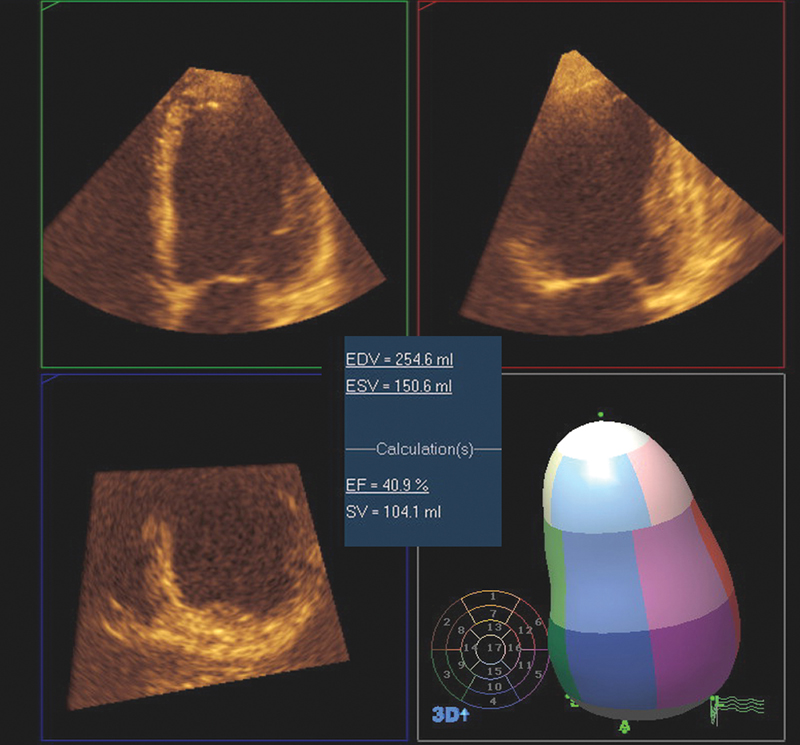

فحوصات تشخيصية لبعض امراض القلب والشرايين التاجية